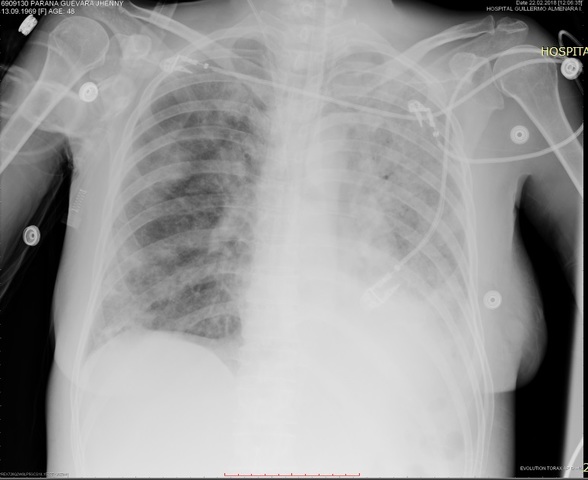

ACTUALIZA ANALITICA, RX TORAX